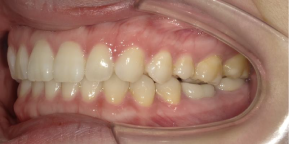

29歳女性のビフォーアフター

| 診断 | 叢生(デコボコがある状態)、過蓋咬合 |

|---|---|

| 治療方針 | インビザラインシステムにて主にIPR(歯と歯の間をわずかに削合してスペースを獲得する方法)を組み込んだ動的矯正治療を行い、叢生を改善後、保定を行う。臼歯部の咬合関係はプランの関係上維持して叢生と前歯部の咬合改善を目指した。 |

| 治療費 ※ | 60万4千円(診断、型取り、PMTC、保定装置を含む料金) |

| 治療期間 | 1年5か月 |

| リスク | 1日20時間以上マウスピースを使用できない場合、歯が動かない可能性がある。装着時や食事時に痛みを伴う。歯肉退縮や虫歯になるおそれがある。また、指導通りに装着できていない場合や適切なブラッシングが出来ていないとそのリスクが高くなる。歯根が短くなることがある。ごくまれに歯の神経が損傷してしまうことがある。過去にぶつけたり深い虫歯治療をしたことがあるとそのリスクはやや高くなる。矯正後には保定装置が必要。適切な使用ができない場合、後戻りの原因となる。将来的に歯並びが動いて再矯正が必要な場合がある。親知らずが正常に生えていない場合、その可能性がやや高くなる。 |

※ 治療費は、治療当時の費用で、現在の費用と異なる可能性があります。現在の費用は治療費のページでご確認くださいませ。